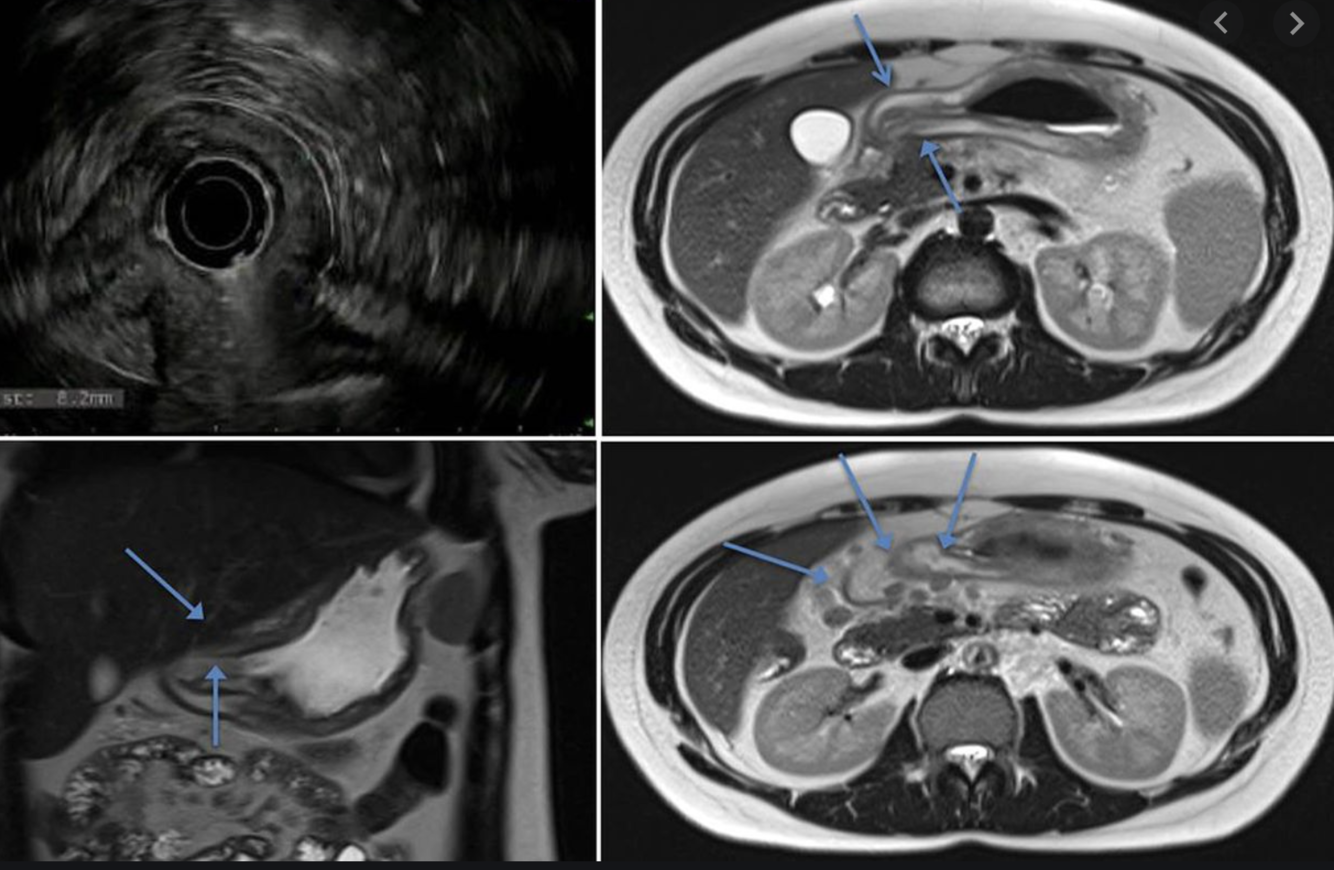

Most common cause of this?

“Double duct” sign = pancreatic adenocarcinoma at the pancreatic head.